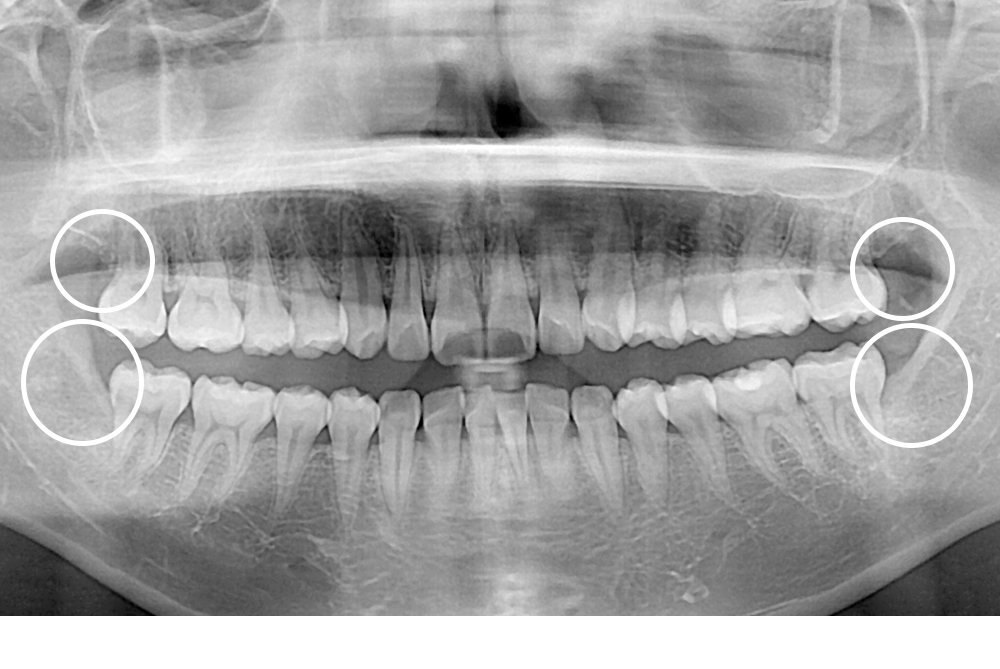

[사랑니] 매복 사랑니 발치

치료전 : 2020-03-24